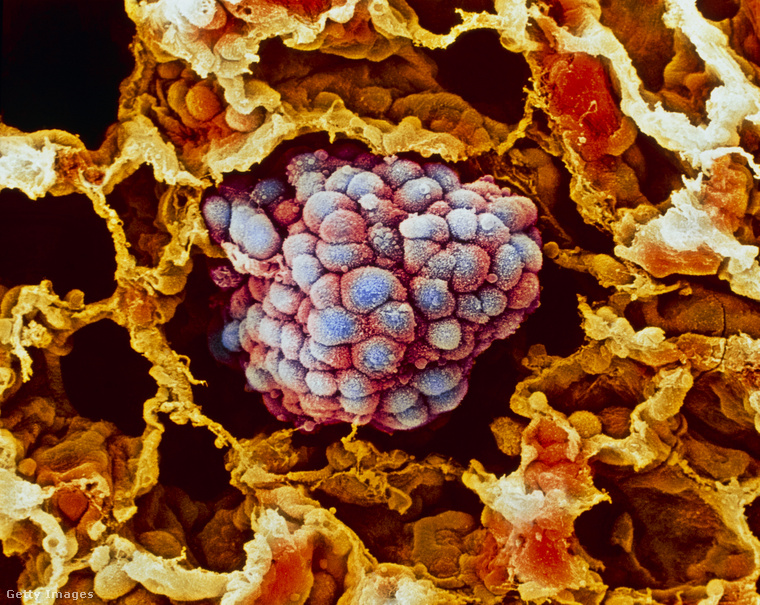

(Borítókép: Tüdőrák. Illusztráció: Getty Images)